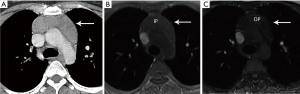

Computed tomography (CT) with contrast is the imaging modality of choice to evaluate thymic tumors due to its high spatial and temporal resolution, ease of access, and convenience. CT can reliably discern location, size/shape, morphology, margins, density, enhancement, and relationship to, or invasion of, adjacent structures (4) (Figure 2). Overall, CT is equal or superior to magnetic resonance imaging (MRI) in the evaluation of mediastinal masses with the caveat that MRI better evaluates thymic cysts or cystic components of tumors (5) (Figure 3).

The role of fluorodeoxyglucose (FDG) positron emission tomography (PET)/computed tomography (CT) in thymic mass evaluation is incompletely defined. False-positive studies can be seen with FDG uptake in non-neoplastic masses, such as in the setting of infection, thymic hyperplasia, or fibrosing mediastinitis. False-negative studies can be seen in certain histological types of thymic malignancy with lower metabolic activity. Additionally, there is lack of technique standardization which results in quantitative variability between studies (8). Given that other prevascular masses such as malignant germ cell tumor and lymphoma are often FDG avid, the presence of a hypermetabolic prevascular mass cannot distinguish between various tumors. There are studies that report that FDG uptake can help predict tumor invasiveness and prognosis. Other studies report FDG uptake as useful in differentiating low-grade from high-grade thymic malignancies; however, other studies report these observations as controversial due to overlapping imaging findings and FDG uptake between low-grade and high-grade thymic tumors (9). Overlapping findings are less common in more aggressive tumors, such as thymic carcinoma, due to higher overall tumor metabolism, with studies reporting that a maximum standard uptake value (SUVmax) of 6 can serve as a cutoff between thymic carcinoma and lower grade thymic tumors (10) (Figures 2,3). However, this threshold cannot differentiate thymic carcinoma from other malignancies such as lymphoma or non-seminomatous germ cell tumor. Finally, PET/CT clearly has a role to detect occult metastasis in hypermetabolic tumors.